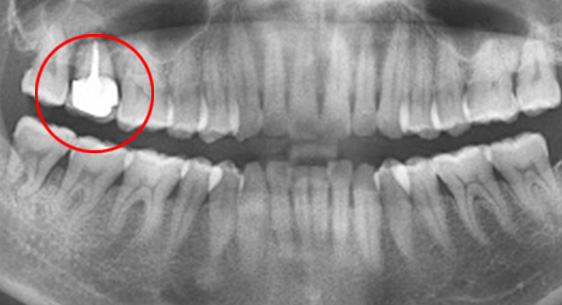

연세고운미소치과는 치아가 흔들린다고 무조건 임플란트를 하지 않습니다. 치조골 상태에 따라 치주치료, 고 난이도 보존치료를 시행합니다. 또한 심각한 충치나 치아 파열로 인하여 발치 된 경우도 상황에 따라 인접치아를 움직여 공간을 닫는 교정치료로 치아를 최대한 살리는 방법을 우선 고민합니다.

치조골이 절반만 남아있어도 치주치료를 통하여 자연치아를 살릴 수 있습니다. 타치과에서 임플란트 수술을 진단받은 경우에도 고운미소치과에서는 임플란트 수술을 안받고 치료가 가능하거나, 생각보다 훨씬 적은 수의 임플란트를 식립 하는 경우가 상당히 많습니다.